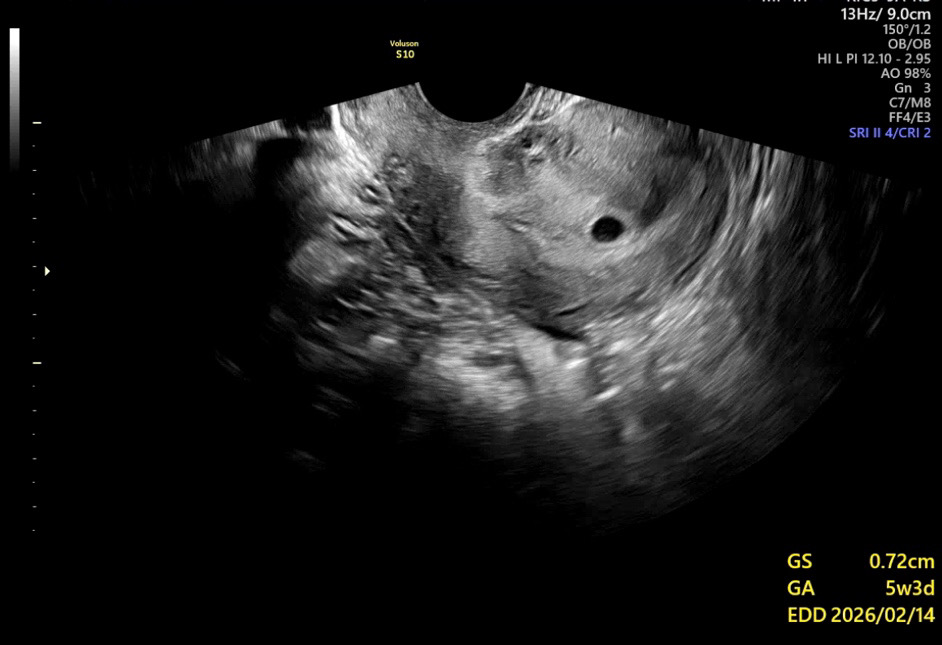

배유제 복용 후 자임 기존 다니던 병원에서 안보인다 하셔서 당일 다른병원도 다녀왔어요!! 기존병원- 난황을 볼 수 있을줄 알았는데 안보이네요 아기집이 작아서 그런지 라고하셨고 아기집 0.7cm 유산방지약 일주일 추가로 받아옴.... 4주5일 아기집 0.3 일주일에 많이 안자람 타병원 - 지금 주수에 아기집이 너무 작다 자기 산모였음 수술 하라고 한다. 아기집이 1.4는 나왔어야했는데 안컸고, 좋지 않다 안보인다 마음 잡아라 다음주에 수술해라 이런경우 다음주에 볼 수 있을까요..? 동영상 돌려다보니 ㅠ 제 눈에 난황같아서 ㅠㅠ 올려보아용

사진 클릭해보면 난황 잘 보여요! 자임은 더 기다려보셔도 늦지 않아요 ㅠㅠ 초기에 좀 느리다고 무조건 비정상임신으로 단정짓는 건 좀 위험한 거 같아요